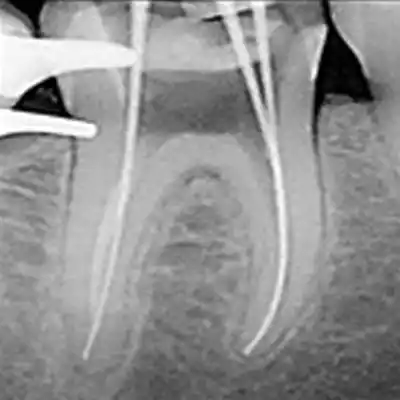

Examen orientado a medir la distancia entre una referencia coronal y el límite apical de la preparación del conducto, guiado por su recorrido y respetando su anatomía.

• =Establecer la longitud de trabajo en procedimientos endodónticos

• =Verificar estructura anatómica de conductos radiculares